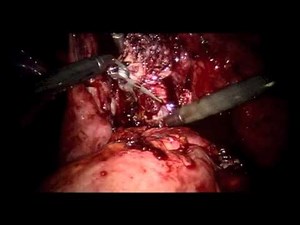

Myomectomy (Surgery for Fibroid Uterus) • Video • MEDtube.net

已浏览 9654 次

2020年2月21日

medtube.net

Step-by-Step Laparoscopic Myomectomy: Overcoming Infertili

…

2024年10月15日